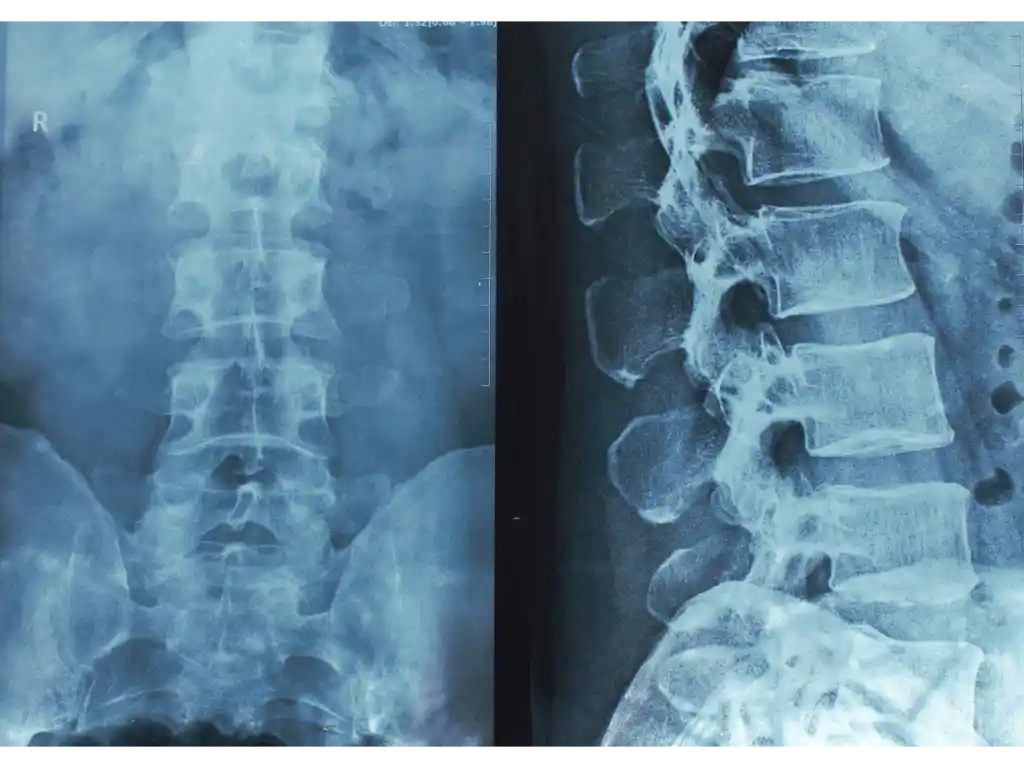

Spinal Cord Injury with Tetraplegia in Young Persons After Diving Into Shallow Water: What has Changed in the Past 10 to 15 Years?

Over the past 30 years, advocates and policy makers started prevention programs to inform people of the high risk of spinal cord injuries (SCI) from diving into shallow water, defined as less than five feet deep. An estimated 80% of shallow diving cases result in SCI, and a significant portion result in quadriplegia (loss of motor function below the upper back or neck). The ThinkFirst program, started in the 1980s, effectively reduced these cases from seven persons a year to only two.

To revisit previous findings, a research team analyzed all SCI cases resulted from shallow diving from June 2001 to June 2019 seen in a specialty healthcare center. They found that:

- Of quadriplegic cases, more than half (55%) were complete injuries, meaning a complete loss of motor and sensory function below injury. Cases of incomplete quadriplegia had higher rates of improved conditions.

- Surgical treatment within 24 hours of admission lowered the severity of quadriplegia.